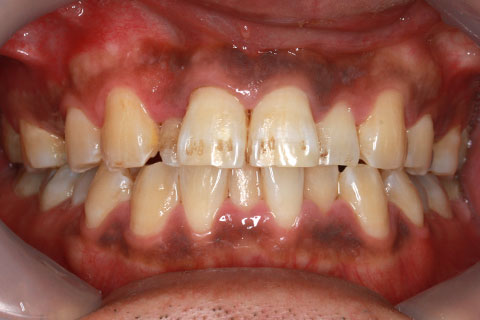

• オールセラミックの症例2

治療前

治療後

年齢・性別

45歳男性

治療期間

2ヶ月

抜歯

なし

治療費

70.4万円

備考

前歯8本の歯列不正によるセラミック治療

治療内容

歯質を削除し、セラミック冠をセメント合着

施術の副作用(リスク)

知覚過敏、歯髄炎、荷重負担